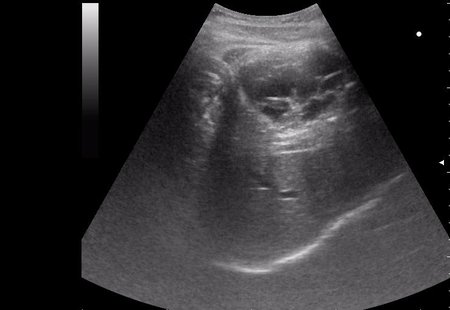

17-летняя девушка с множественными поражениями печени

3.JPG

абсцесс передней брюшной стенки (через 2 недели п.о.)

нагноение остаточной полости